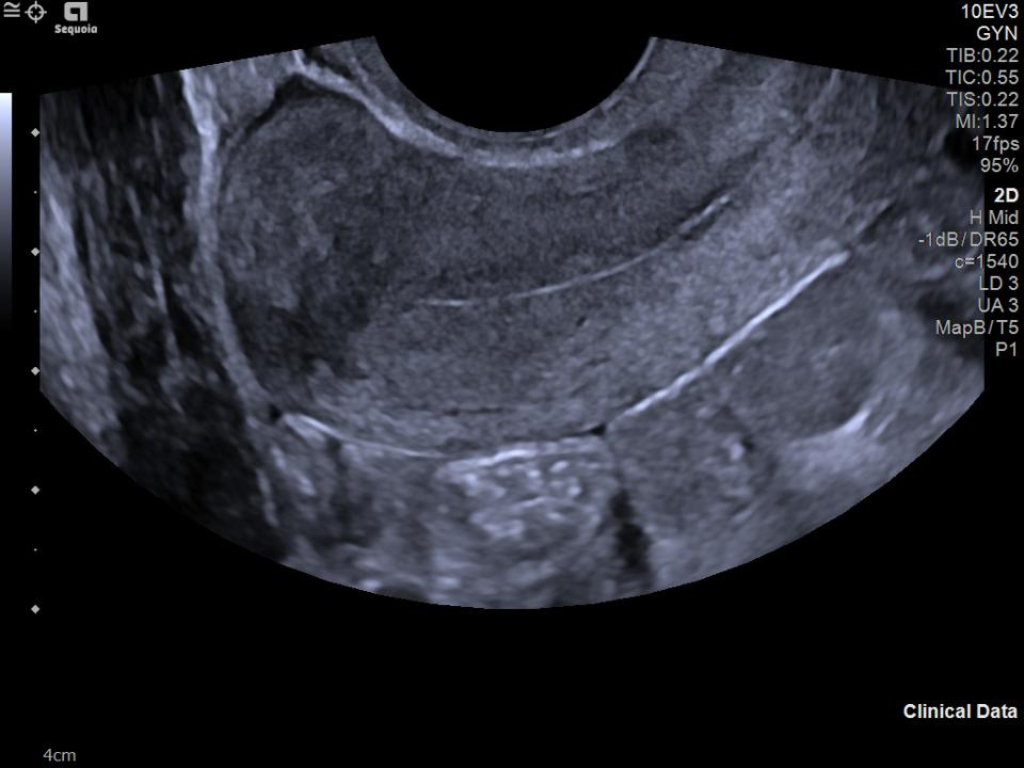

The ACUSON Sequoia is an advanced diagnostic tool that integrates cutting-edge technology and AI-powered applications to streamline diagnostic processes. This system is designed to cater to patient-specific needs, ensuring accuracy and efficiency in various clinical settings such as Radiology, OB/GYN, Shared Service and beyond.

The latest updates on ACUSON Sequoia use the power of groundbreaking AI for abdominal cases, includes advanced breast visualization to deliver new levels of image quality confidence, and tackles the toughest challenges in musculoskeletal imaging, all while saving your team from needless strain and pain.

Boost your clinical confidence with a system designed to enhance your expertise. The ACUSON Sequoia gives you the power to know more by maximizing the sensitivity and depth of your scans, while reducing variability across patients, systems and users.

ACUSON Sequoia’s InFocus imaging architecture eliminates the need for conventional focal zones to create a fully focused image faster than conventional systems. Our InFocus technology applies to all imaging transducers and exam types giving you consistent imaging across clinical segments. Some of the benefits are:

A clearer, deeper perspective with optimal acoustics for each clinical use case. Expand your assessment with advanced tools that take ultrasound beyond its traditional role.